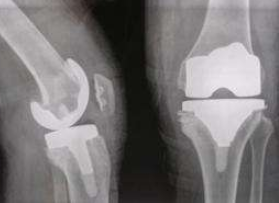

用于人工关节的材料首先要求其具有优异的生物相容性、不产生任何的毒副作用;同时还应具有寿命长、不磨损、不产生松动等特性。聚酰亚胺材料是我国自行研发的一类高分子聚合材料,具有优良的物理化学稳定性、易加工性、表面粘附性、自润滑性、生物力学性能,是体内植入材料的理想选择。

通过体内植入试验、皮肤致敏试验、细胞毒性试验和遗传毒性评价等生物毒理试验,证实碳纤维增强的聚酰亚胺材料生物安全性良好,对生物体无毒副作用,可以作为人工关节的生物材料,应用于临床。